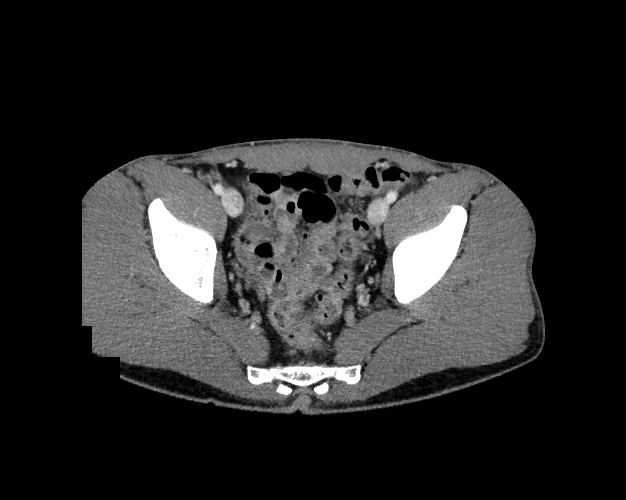

Pelvis

Covers pelvic MRI anatomy.